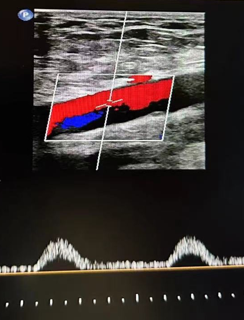

心功能室的李月医生在检查时敏锐捕捉到异常信号:双侧股总动脉血流频谱呈特征性“小慢波”——这通常是大血管严重狭窄的强烈提示。